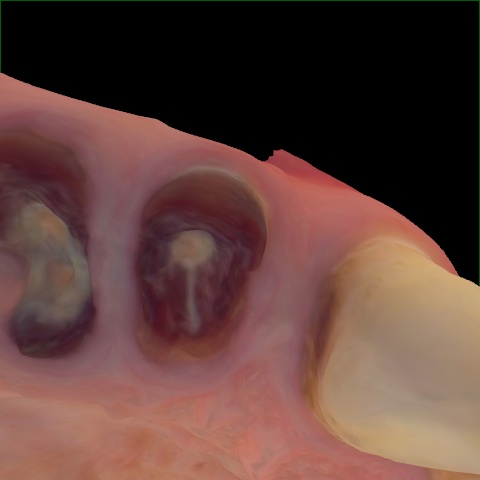

Incorrect Quality Level

The reference annotation for this image is

None

.

Please select the correct quality level.

Annotated as "Good"